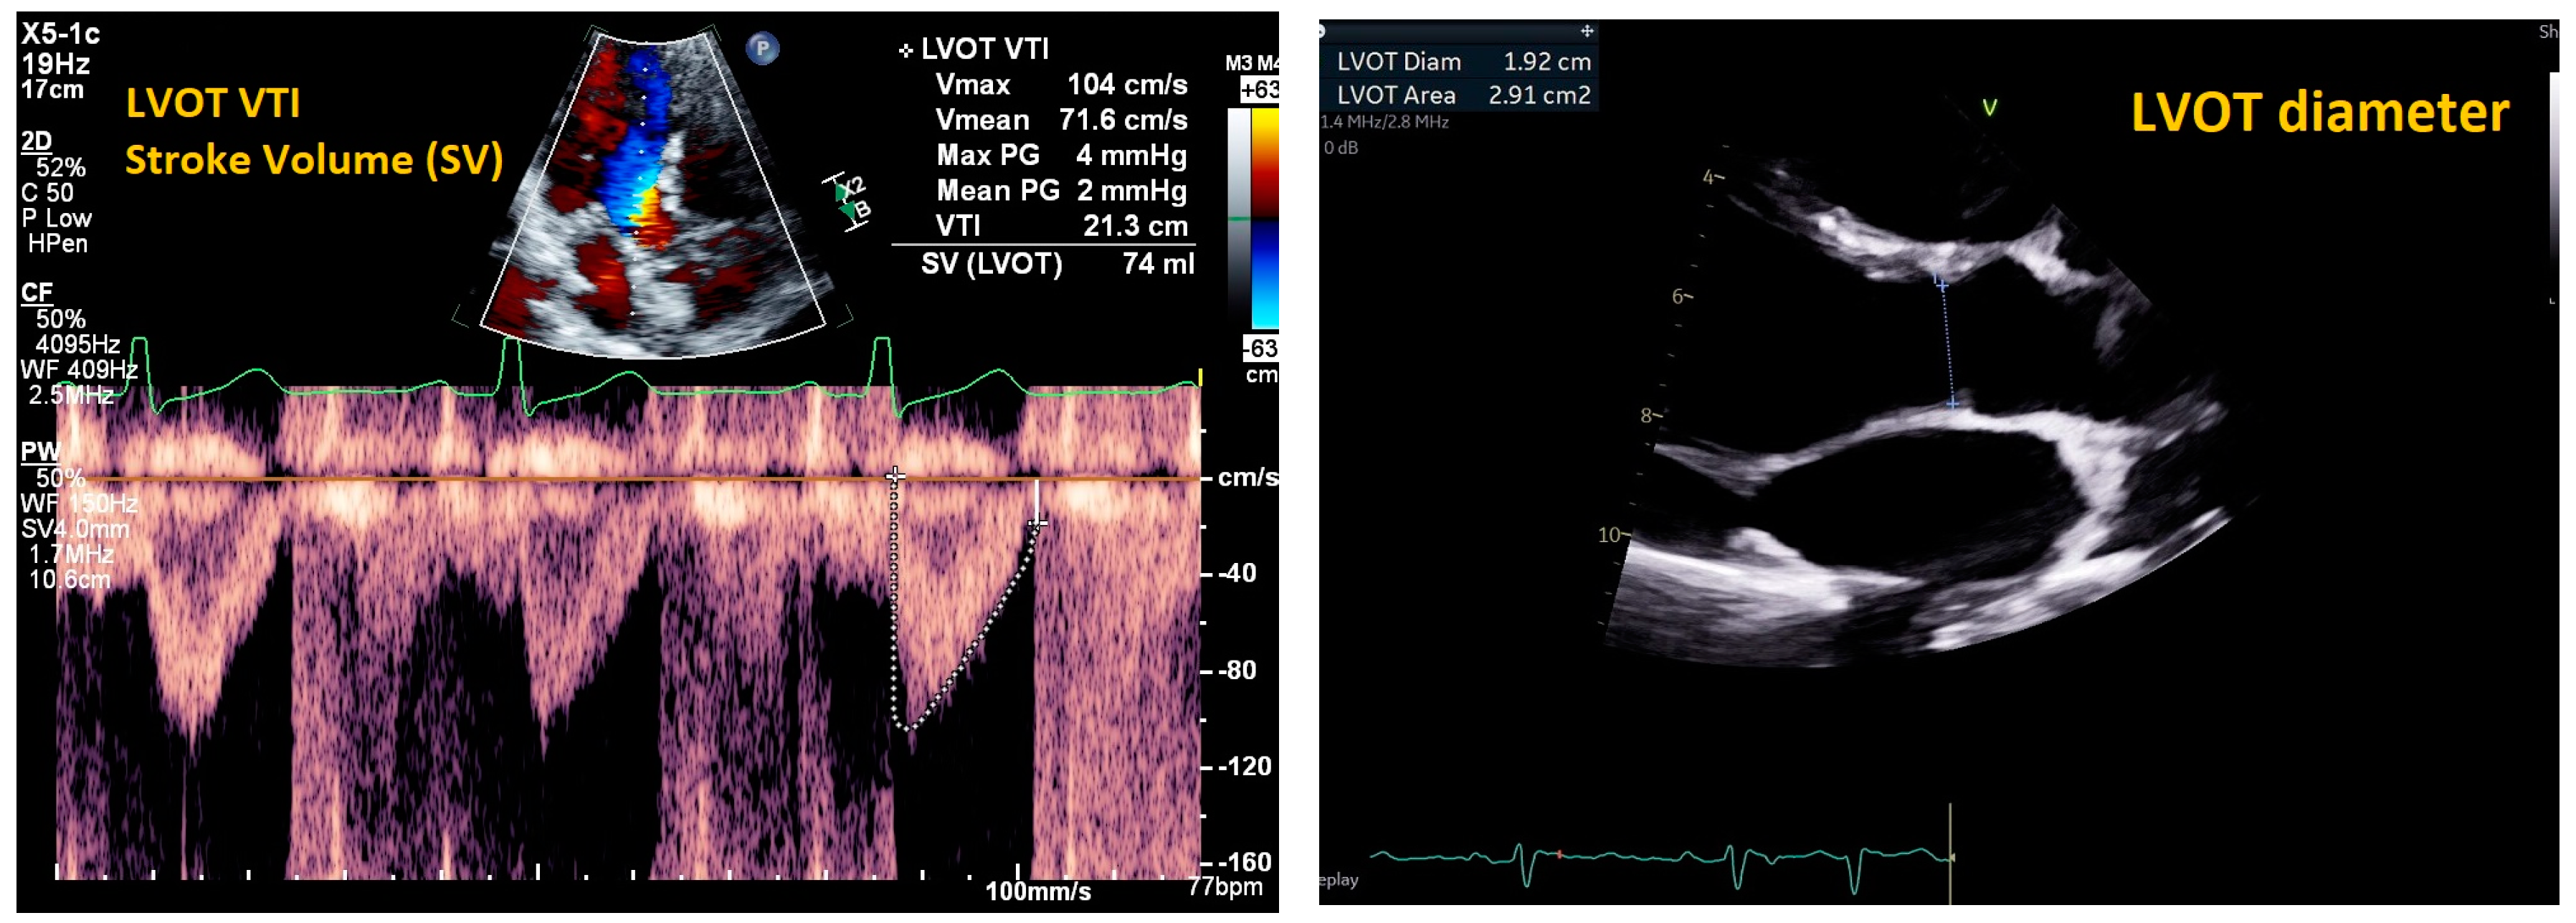

2. Cardiac Ultrasound

- Beigel, R.; Cercek, B.; Arsanjani, R.; Siegel, R.J. Echocardiography in the use of noninvasive hemodynamic monitoring. J. Crit. Care 2014, 29, 184.e1–184.e8. [Google Scholar] [CrossRef] [PubMed]

- Patel, N.; Durland, J.; Awosika, A.O.; Makaryus, A.N. Physiology, Cardiac Index; StatPearls Publishing: Treasure Island, FL, USA, 2024. [Google Scholar]

| Mitral E/e’ ratio estimated from the E wave velocity of the mitral inflow Doppler envelope and the tissue Doppler e’ wave velocity at the mitral annulus (septal and/or lateral) | E/e’ ≤ 14 |

|

| |